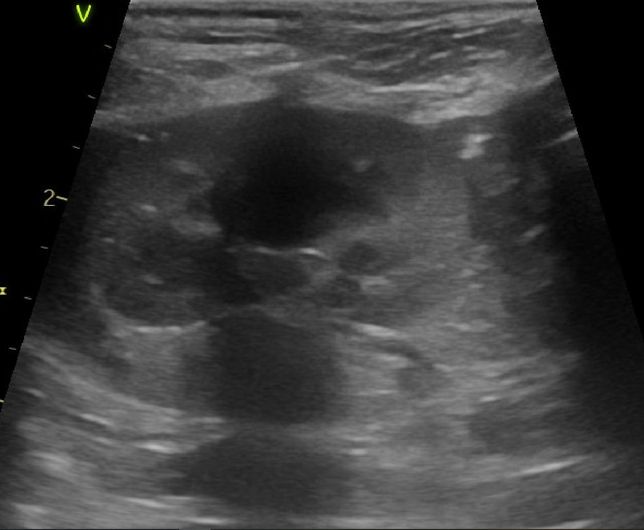

- 반려동물 건강반려동물Q. 강아지 신장결석 칼슘옥살 스트루바이트 둘중 어느것 같아보이는지요?강아지 신장결석 칼슘옥살 스트루바이트 둘중 어느것 같아보이는지요? 그냥 보시기에 만약에 판별이 가능하다면 알려주심 정말 감사하겠습니다. 병원만 3곳 다녔고 소변검사에 방광천자 제외하고 전부다 해봤는데 현재 6개월이 넘어갔는데 무슨 결석인지도 모르는 상태고 결석 크기는 신장 양쪽에 점점 커지고 있는 상황이라 이대로는 가만 있을수가 없어서 이렇게나마 질문글 올립니다.. 부디 알려주심 정말 한생명 살리는샘치고 정말 감사하겟습니다.